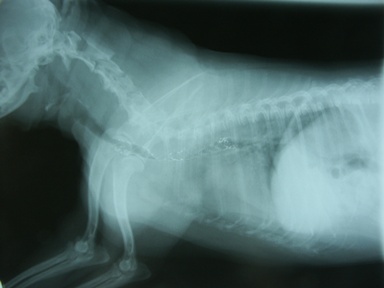

診断 気管虚脱GradeIV(図4)

図4 症例1の初診日。気管陰影ほぼ消失。